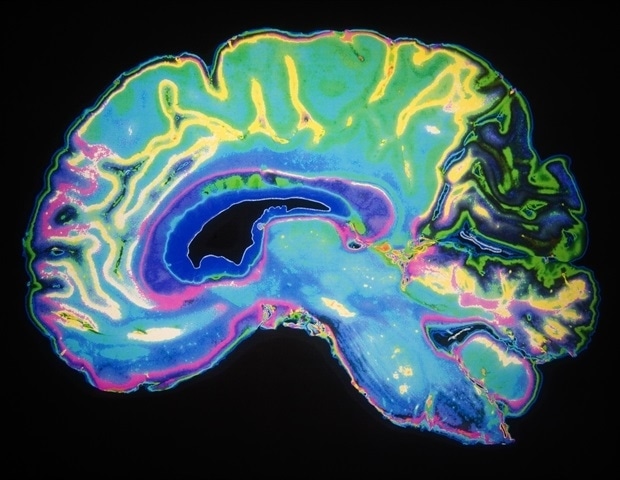

The authors stress the importance of recognizing the multifaceted nature of sleep. “Sleep is made up of many dimensions, not just how long we sleep,” said Aurore Perrault. “By analyzing more than 700 young adults, we discovered five distinct ‘sleep profiles’ based on reports of sleep duration, disruptions, and medication use. Each profile carried its own distinctive links to health, lifestyle, and cognition, and even showed unique neuroimaging traits using functional MRI.”

The findings emphasize that understanding sleep requires a holistic view. According to Valeria Kebets, “The dominance of mental health markers in most of the profiles is not surprising, as sleep is one of the five key domains of human functioning likely to affect mental health.” The study reveals that sleep experiences are intricately tied not only to health and behavior but also to the underlying neural architecture of the brain.